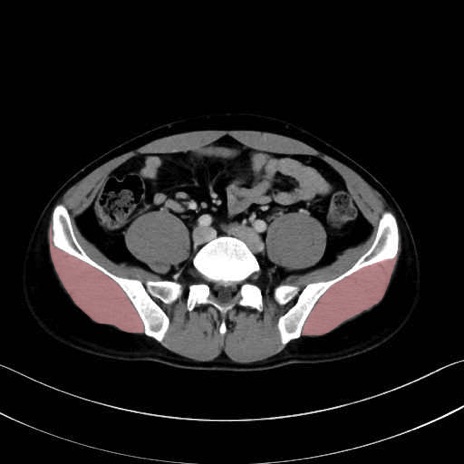

中殿筋 (Gluteus medius)